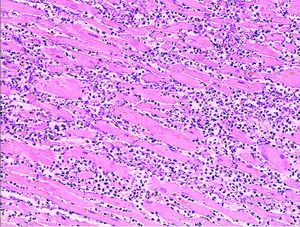

Histopathology

Microscopy image (magn. ca 100x, H&E stain) from autopsy specimen of myocardial infarct (7 days post-infarction).